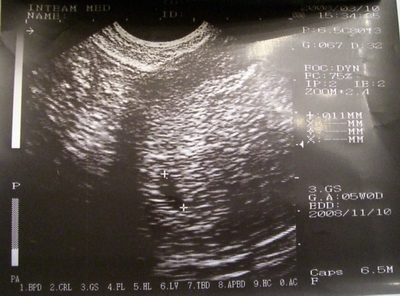

Megvizsgált és vaginális UH-t is végzett. A "diagnózis": Megnagyobodott uterus cavumában egy

9x5.6mm szabályos petezsák látható, fundusban jó helyen. Subcharialis haematomára utaló jel nincs. Embrio még nem ábrázolódik. Biometriai adatok alapján Grav. s. 5-6.